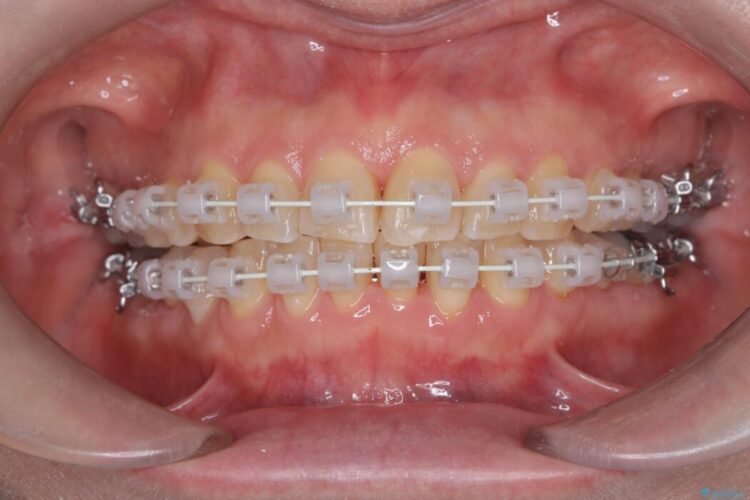

患者様のご希望と状態に合わせ、目立ちにくい審美ワイヤーにて治療を行うこととしました。

今回の矯正治療では、歯の色に近い目立たない審美ブラケットとワイヤーを使用しました。